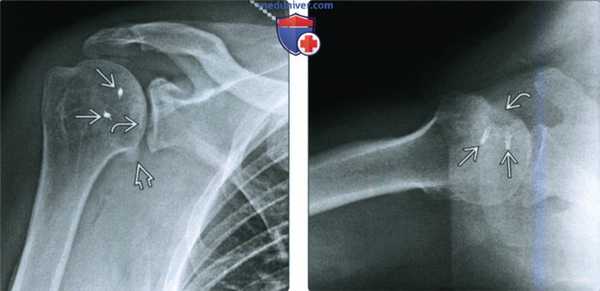

(Слева) На рентгенограмме Грасхея после операции по поводу рецидивирующей задней нестабильности после нескольких задних вывихов видны два шовных фиксатора в проекции над головкой плечевой кости. Кроме того, имеется симптом бороздки В и старая мозоль В, исходящая из обратного перелома Хилла-Сакса.

(Справа) На осевой рентгенограмме у этого же пациента снова видно, что два шовных фиксатора В находятся во вдавленном обратном переломе Хилла-Сакса. У пациента перемещено сухожилие подлопаточной мышцы для предупреждения рецидивирующих вывихов.

• Проекция Грасхея/Ниера:

о Головка плечевой кости чрезмерно перекрывает край суставной впадины

о В нормальной ситуации при правильном положении в проекции Грасхея видна щель между головкой и суставной впадиной

• Аксиллярная проекция:

о Смещенная кзади головка плечевой кости

о Лучшая проекция для подтверждения заднего вывиха

о Часто блокирована: головка плечевой кости упирается в задний край суставной впадины:

- Задний край суставной впадины находится напротив обратного дефекта Хилла-Сакса

о Задний перелом Банкарта:

- Перелом заднего края суставной впадины:

30% задних вывихов